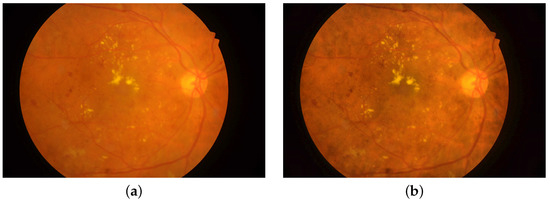

In this work two, public image datasets of retina images are used to train and evaluate the proposed DLN. These sets enclose retinal images captured by two screening techniques; fundus photography and optical coherence tomography. The Indian Diabetic Retinopathy Image Dataset (IDRiD) is the fundus retinography image set [50]. The Kaggle Dataset [49] is the OCT retinal image set used in this research. Figure 1 illustrates sample images captured with fundus camera and OCT for healthy and DM-diseased retina.

Figure 1. Sample retinal images: (a) Healthy; (b) DM-diseased. Upper row: fundus images from the IDRiD dataset. Lower row: OCT images from the OCT dataset.